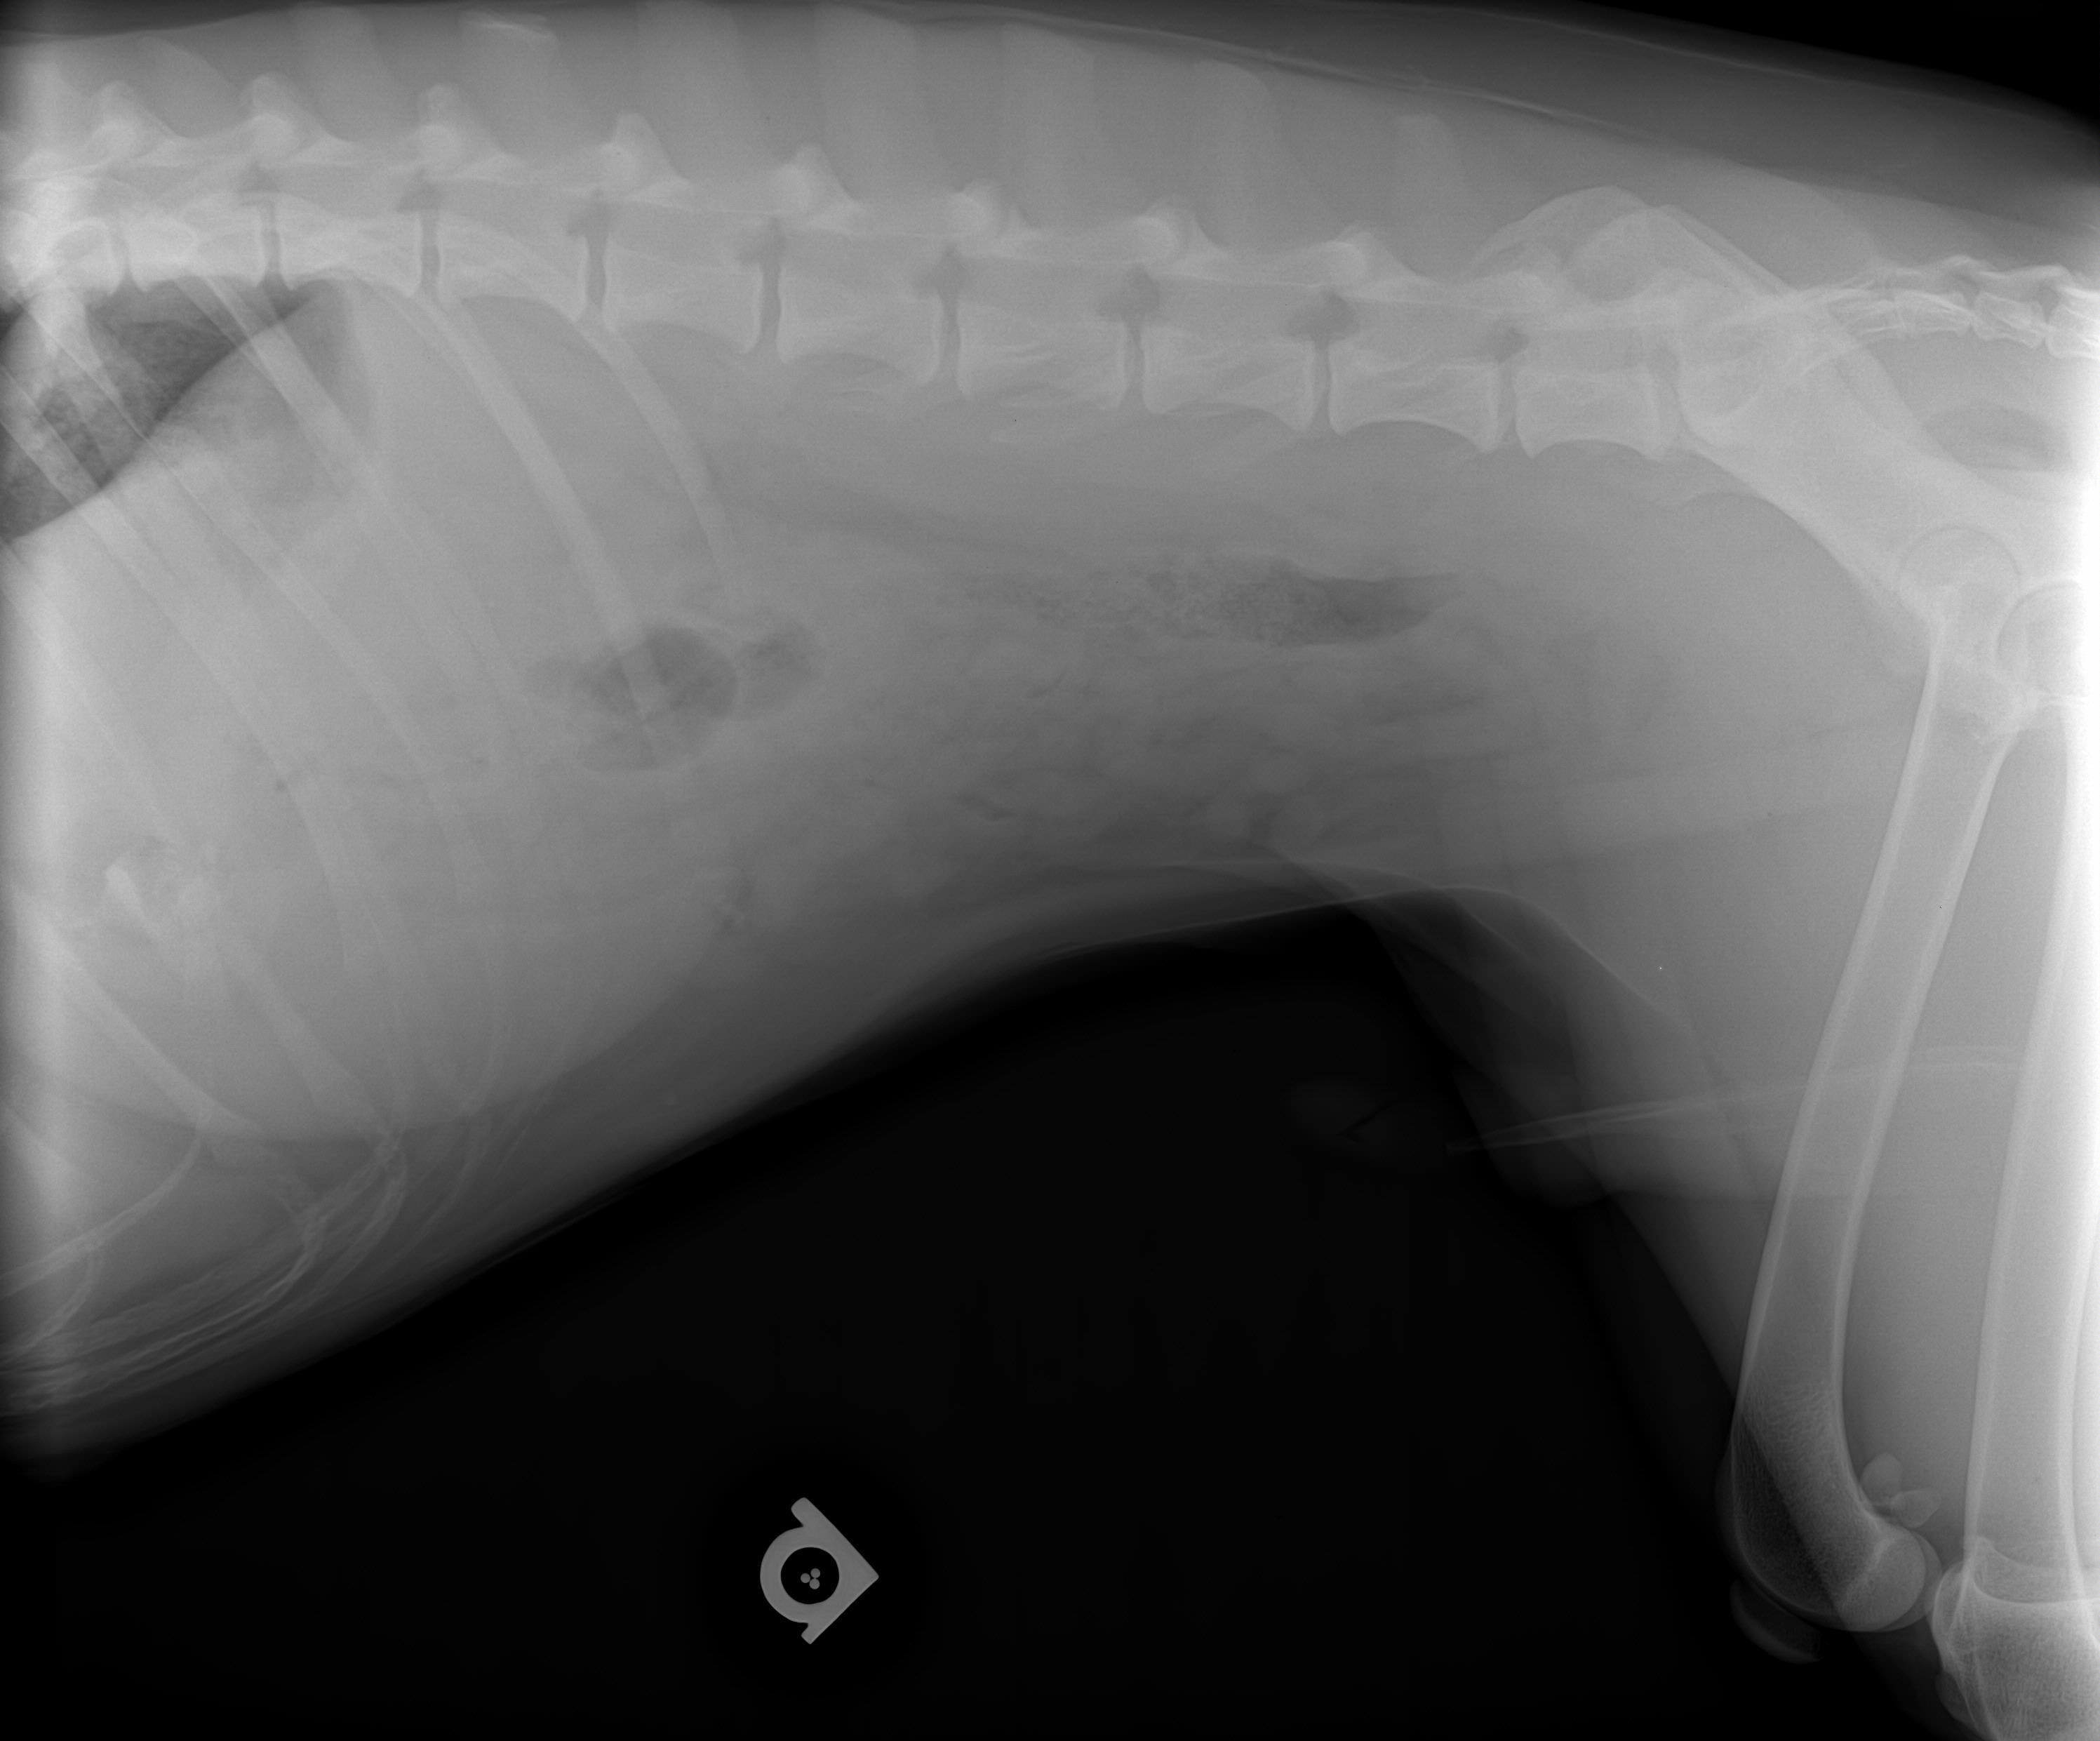

Friday Kyro swallowed big bone off street. Sat & Sun lot of Diarrhea & some vomiting. Sun an Emergency Vet took X ray. Emergency Vet saw piece in stomach. Prescribed Metronidazole & Famotidine, suggested 1/4 cup of rice & 1/4 cup of chicken as feedings which I did a few. Today my Vet said NO rice but feed chicken, pumpkin and peas. My Vet did NOT see bone in stomach. Sunday only slight water as bowl movements. Today no bowl movements. Kyro eating & acting normal. No extended stomach or delicate